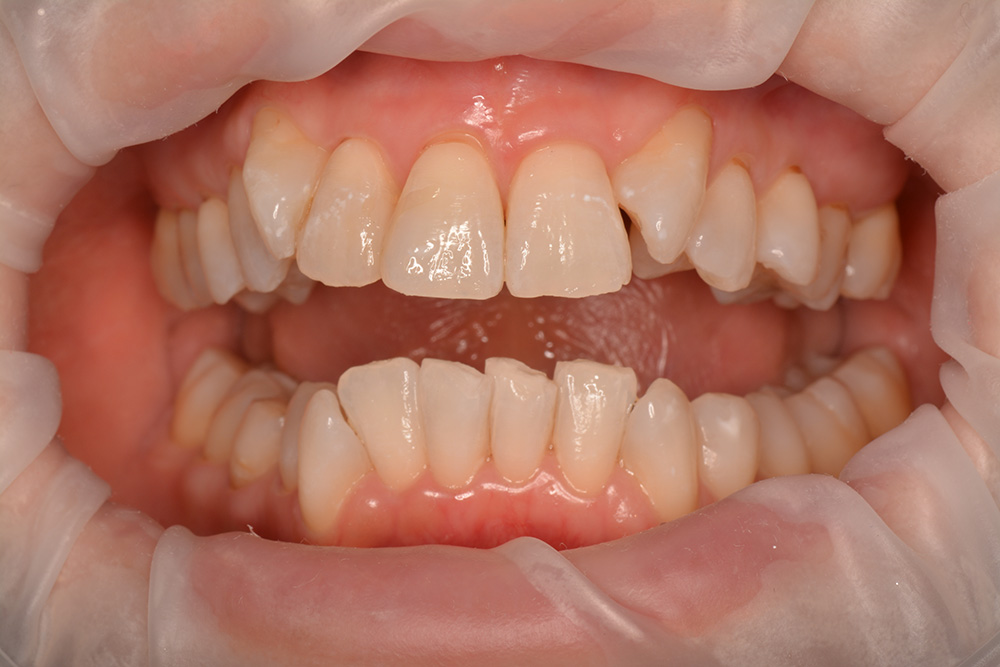

術前

術後

世代・性別

30代女性

主訴

歯がしみる時がある

治療内容

セラミックインレー

治療期間

2回

治療費

66,000円(税込)

治療のリスク

強い咬合力や衝撃によって、欠けたり割れたりすることがある